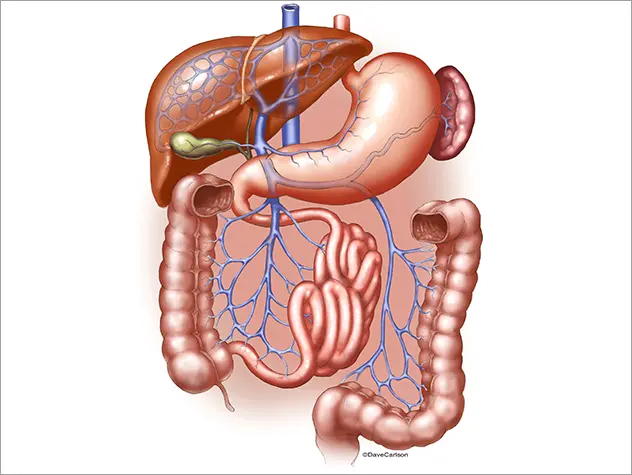

The patient’s severe thrombosis required months of multidisciplinary care and the transplantation of his liver, stomach, large intestine, small intestine, pancreas, and kidney.